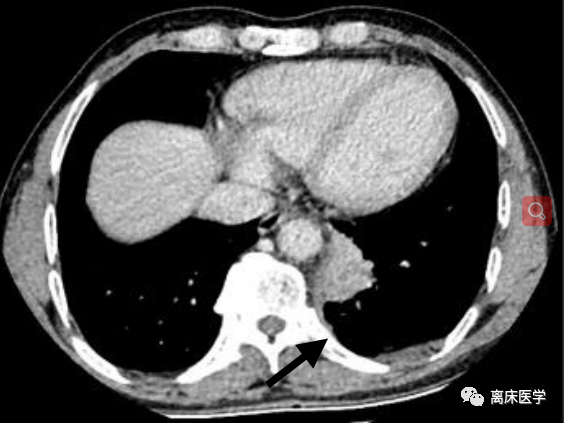

男,63 岁, CT 示左肺下叶团块影,边缘呈平直征(箭头处)。